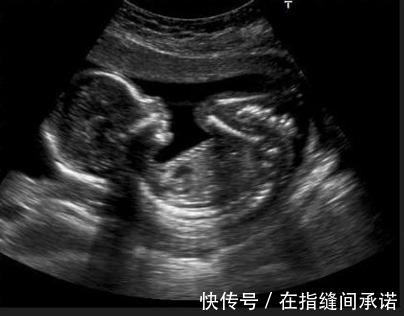

第一是胎动明显胎动,是胎儿在孕妈肚子里运动。孕妈感受到胎动明显,其实很大程度上反映着胎儿发育良好,营养充足。胎儿发育得好,力气自然就大,当然智力发育也不会差。所以,如果孕妈妈感受到胎动明显些,就意味着胎儿智力发育还不错。

胎动一般出现在怀孕四个月左右,当然也有早还有晚,每个孕妈妈的情况不同。有的孕妈以为胎动出现得早,胎儿就聪明,如果胎动出现晚,胎儿智力发育也一般。其实这种说法是错误的,并没有任何的科学根据。这就跟小孩子出牙有早有晚,走路有先有后,说话有早有晚是一样的道理。跟智力发育没关系。